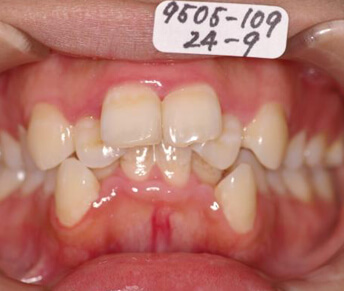

- 見えにくい矯正装置

(セラミック、ブラスチックブラケット)

メリット

- ・装置が目立たない。

デメリット

- ・装置とワイヤーの摩擦抵抗が大きい(滑りが悪い)ので歯が動きにくく、治療期間が長くなる。

- ・装置がセラミックやプラスチックなので金属製に比べ強度が低いので、壊れにくくする為に装置が大きく、違和感が強く口内炎もできやすい。

- ・大きく頑丈に作られていてもやはり強度が低いので装置が割れたり、外れたりする。その度に装置をつけ直す事になり、治療期間が長くなり易い。

- ・装置が壊れやすいので強い力をかける事が難しく、正確に歯をコントロールして良い治療結果得るのが難しい。